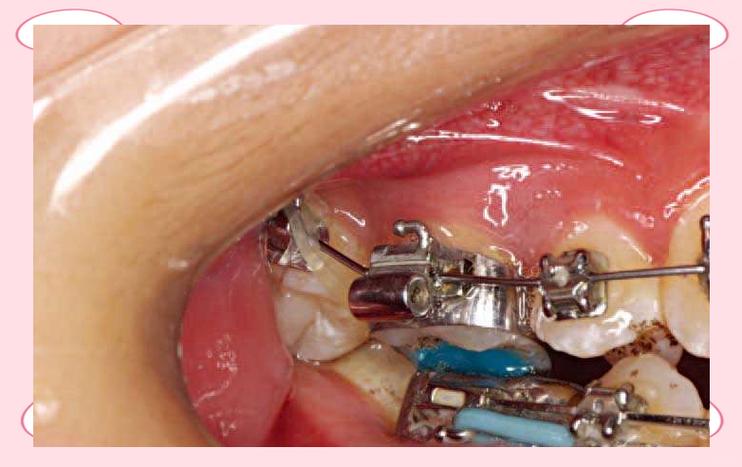

(图片来源网络,侵删)- 在带环就位的同时或之后,立即用探针、雕刻刀或洁治器仔细去除从带环边缘溢出的多余粘接剂。

- 确保牙齿与带环的接触点(邻间隙)没有粘接剂残留,否则会导致食物嵌塞、压迫牙龈甚至龋坏。

- 检查并清理带环内部的粘接剂,避免影响后续附件的安装。